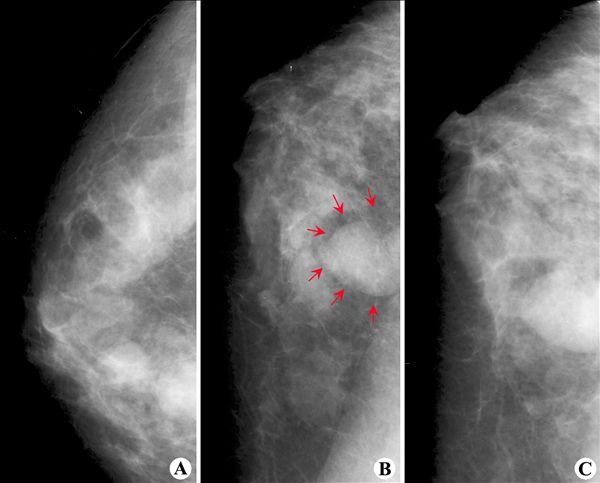

多发乳腺囊肿-X线

【X线钼靶摄影图片】:

【影像表现】:钼靶X线(A~C)示乳腺内见圆形或椭圆形、边缘光滑、密度均匀的致密影;可见“透明晕圈”征(B,↑)。

【影像诊断】:多发乳腺囊肿。